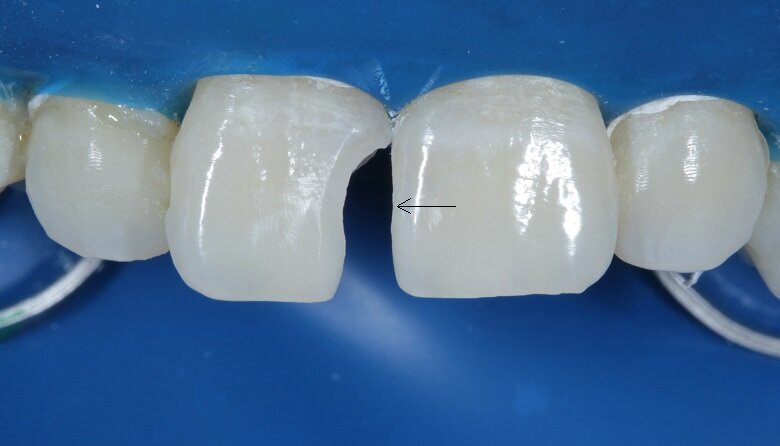

A sectional matrix was then placed in between the teeth (Fig 13). Proximal view of the same depicts that the band was placed and adapted in a manner to achieve tight contacts without overhangs (Fig 14). A proximal wall was built with the help of this band with A2 enamel shade (Fig 15). On this shell, A2 dentin layer was added to give the internal anatomy (Fig 16).

Body and final enamel layer were subsequently added (Fig 17). Immediately after the removal of dam, a picture was taken (Fig 18) to go ahead with the final minor changes in the finishing and polishing protocols to achieve bilateral symmetry. Secondary and tertiary textures were given with a red grit bur using a contra-angled handpiece on a micromotor at slow speed.

Discs and rubber cups were used for the final polishing protocol. Bilateral symmetry was then achieved (Fig 19). A lateral view of the teeth depicted the surface texture (Fig 20). The patient was then recalled after 48 hours for a check-up (Fig 21).